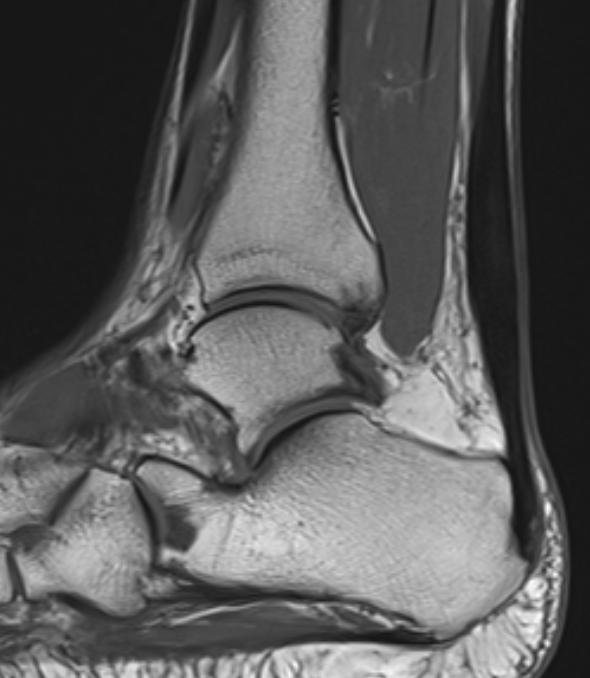

MRI

Tendon thickening

Thickening of the tendon with some intra-substance degeneration / partial tearing